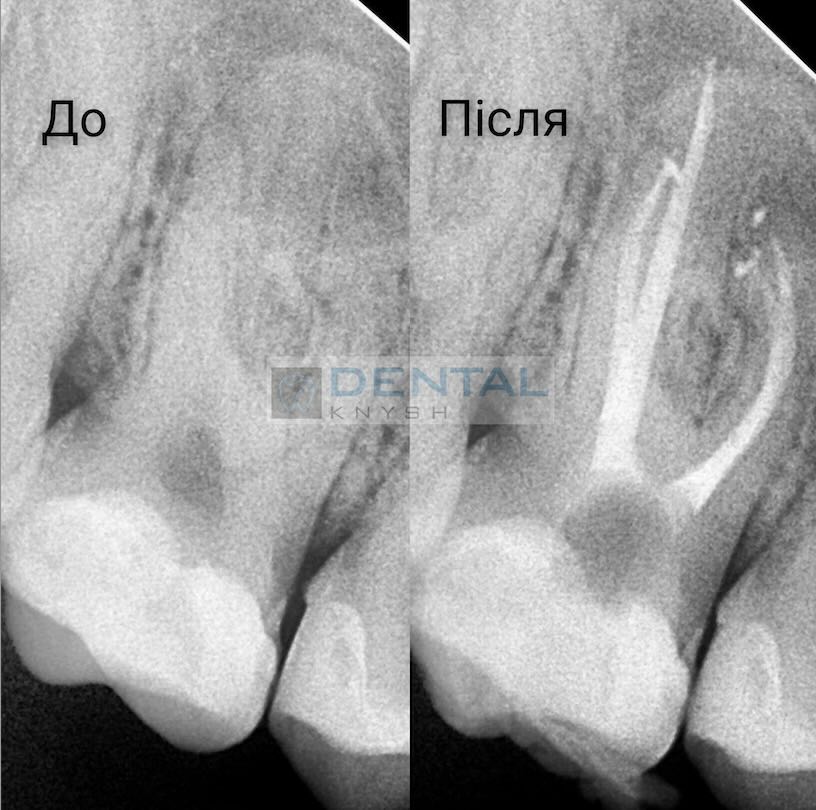

„Leczenie kanałowe pod mikroskopem daje najlepsze wyniki leczenia bez żadnych zastrzeżeń.

Nie każda klinika ma mikroskop do leczenia stomatologicznego, ale w przyszłości mikroskop będzie koniecznością. Im lepszy widok pola pracy, tym lepsze wyniki leczenia.

Początkowo fotele dentystyczne były w tym celu uzupełniane lampami, ale wraz z pojawieniem się mikroskopów stomatologia weszła w nowy etap rozwoju”.

Fotorelacje